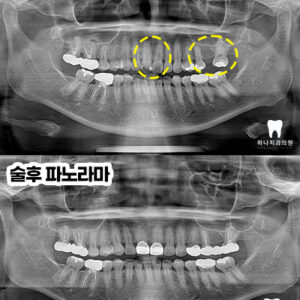

울산치과추천 타 치과 임플란트의 지속적인 통증 치료

울산치과추천 타 치과 임플란트의 지속적인 통증 치료   안녕하세요! 하나치과입니다~:) ​ 임플란트는 1960년대 스웨덴의 정형외과 의사였던 브레네막 교수님에 의해 개념이 도입되고 치과 영역에 조심스럽게 활용되기 시작합니다. ​ 초기에는 치과용 임플란트가 성공률이 증가하고 장기간 유지하면서 성공적으로 기능하는 것을 본 치과 의사들이 믿음을 가지면서 대중화되기 시작하는데요. ​ 이렇게 발전을 거듭해오면서 장점이 있는 더보기…